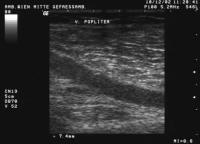

Duplexsonographie - V. poplitea

Abbildung 5: B-Bild-Darstellung der Vena poplitea im Längsschnitt

Keywords: DuplexsonographieVena poplitea